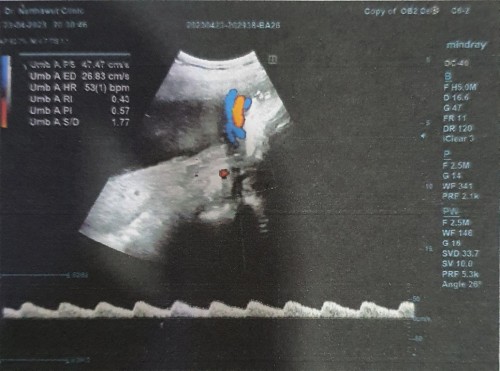

สายสะดือพันคอ พอดีวันนี้ไปหาหมอมาตามนัดปกติค่ะ แต่ที่เป็นกังวลคือ หมอซาวน์แล้วพบว่าสายสะดือพันคอน้อง

อยู่ 2 รอบ มีแม่ๆคนไหนเคยเจอแบบนี้บ้างคะ จะเป็นอะไรไหมน้องจะดิ้นจนหลุดเองได้ไหมคะ แต่ที่ถามคุณหมอเขาก็บอกว่าไม่อันตราย แต่ก็อดกังวลไม่ได้ค่ะ ส่วนน้ำหนักน้อง 2495g อัตราการเต้นของหัวใจก็ปกติดีค่ะ ตอนนี้ 33+2W แล้วค่ะ